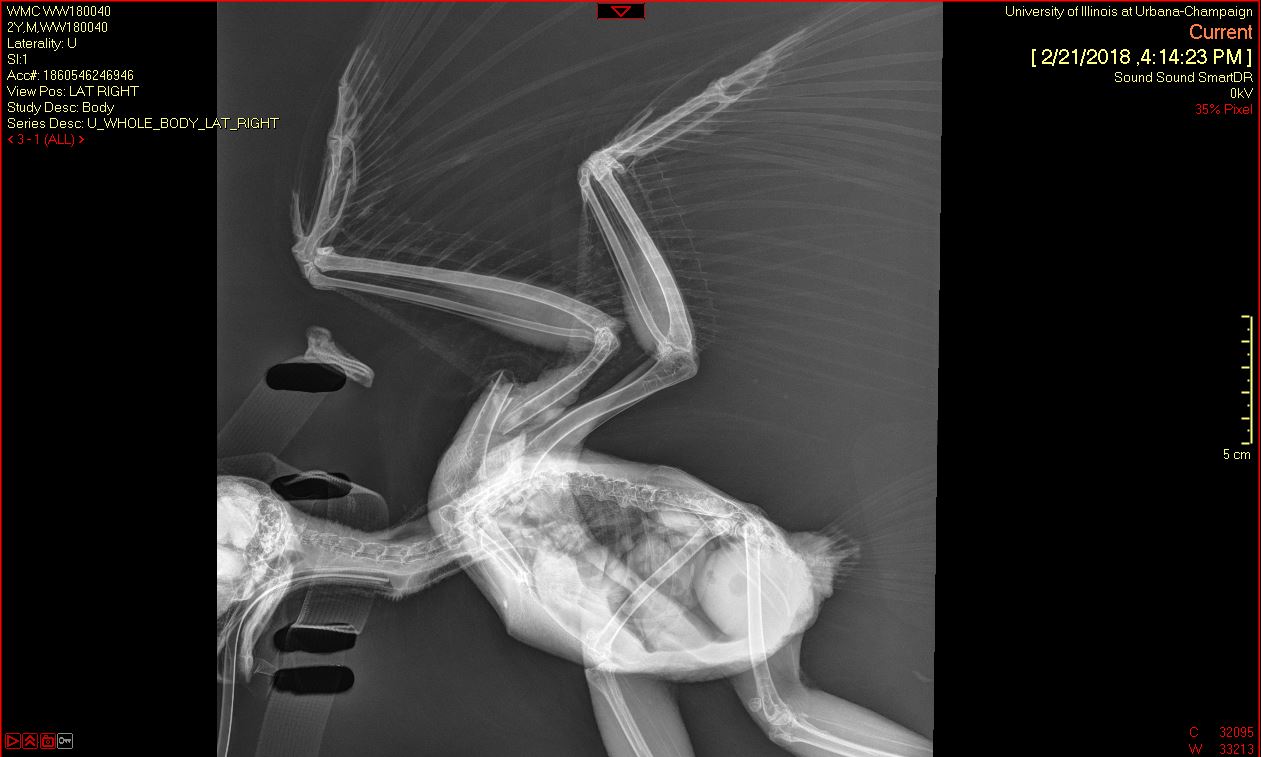

A Barred Owl was transferred to the Wildlife Medical Clinic from a nearby veterinary clinic on February 20th after being hit by a car on February 18th. In their initial exam, the team noticed an open fracture on the middle of the right humerus of the wing. Radiographs (x-rays) showed that the wing had been rotated a complete 360 degrees!

Once the wing was rotated back into normal position, the team had to wait to assess whether the portion distal to the rotation (closer to the wing tip) still had healthy blood supply. Once this was ensured, they determined the owl was a good candidate for surgery to repair the humeral fracture.